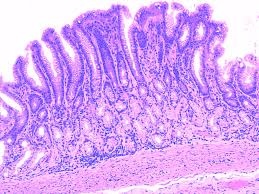

If you have been diagnosed with adenocarcinoma cancer, you have a cancer that developed in one of the glands that lines the inside of your organs. What are the names of gastric glands? - Quora

What are the names of gastric glands? - Quora from qph.fs.quoracdn.net